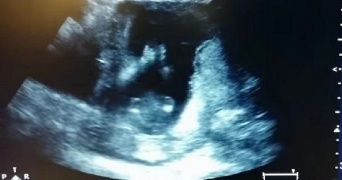

まるで生まれてくるのが待ち遠しくてたまらないかのように、お母さんのお腹の中で手拍子をする赤ちゃん。そんな愛らしくも驚きの映像が話題を呼んでいます。 お腹の中の胎児を透かして見ることができる、いわゆる超音波検査で映し出されたのは、14週齢の胎児。 なんと、お母さんの歌う『幸せなら手をたたこう』に合わせて、小さな手でリズムをとっています。 Clap your hands, baby announcement. 出典: You...